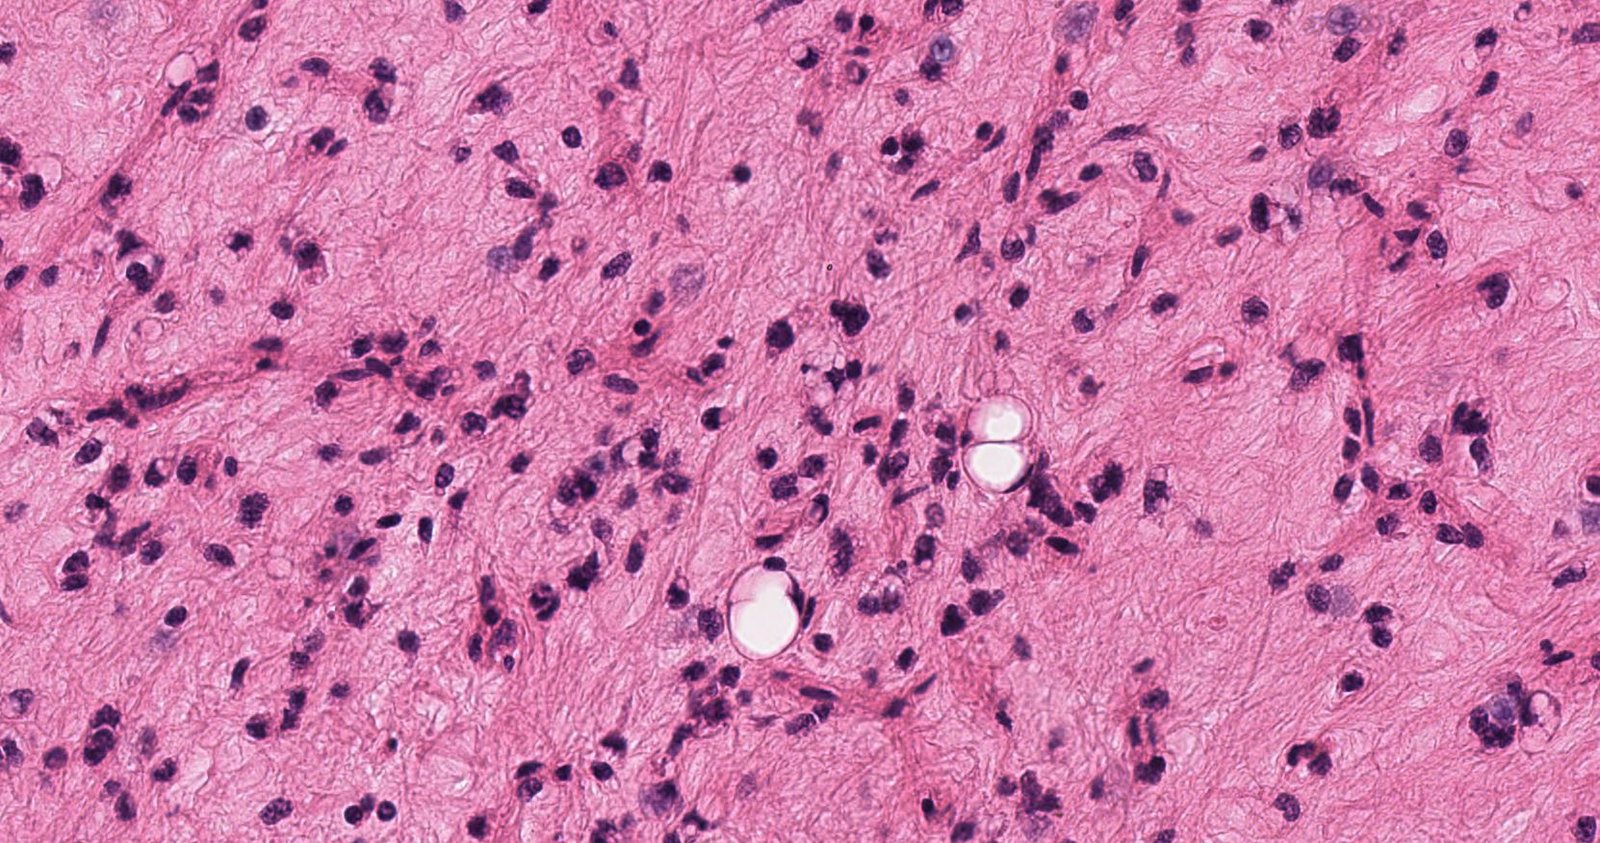

Unknown Case Case: ThighMass2